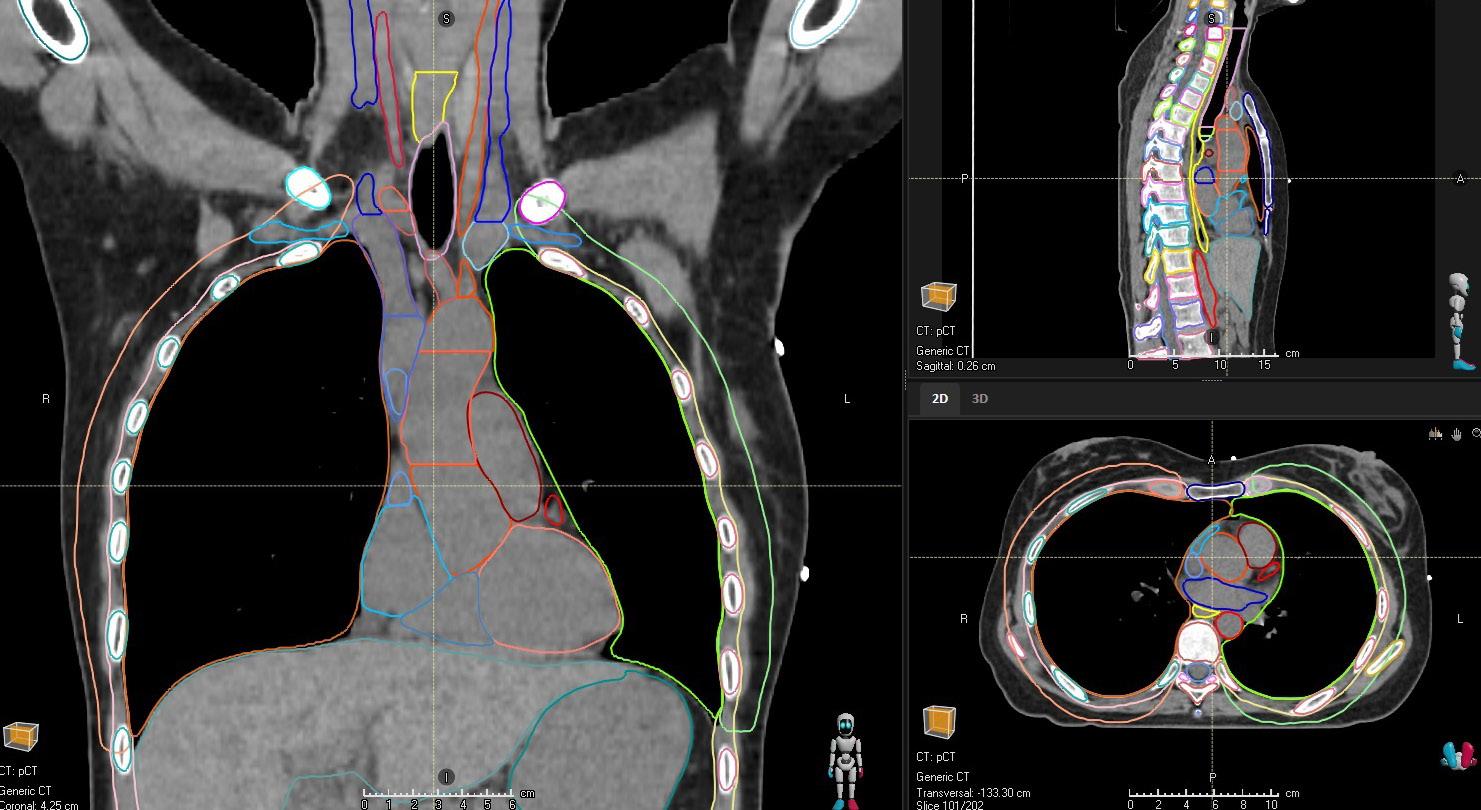

Deep learning capabilities in RayStation®* help make image segmentation quicker and more consistent. A high-speed GPUpowered algorithm is capable of producing consistent segmentation results using guideline-based segmentation models that have been trained and evaluated on curated data for different body sites.

THORAX/ABDOMEN CT

STRUCTURES

BrachialPlex_L Esophagus

BrachialPlex_R Glnd_Thyroid

Bronchus_InterM Heart

Bronchus_Main _L Heart_Inferior_Left_PA

Bronchus_Main_R Humeral_Head_L IMPROVED Ribs_L NEW

Carina Humeral_Head_R IMPROVED Ribs_R NEW

Cartlg_Costal_L NEW Humerus_L NEW

Cartlg_Costal_R NEW Humerus_R NEW

Clavicle_L NEW Kidney_L

Clavicle_R NEW Kidney_R

CW_2cm_L NEW Liver

CW_2cm_R NEW Lung_L

CW_Anatomical_L NEW Lung_R

CW_Anatomical_R NEW

Pancreas

Scapula_L NEW

Scapula_R NEW

SpinalCanal

Spleen

Sternum

Stomach

Trachea